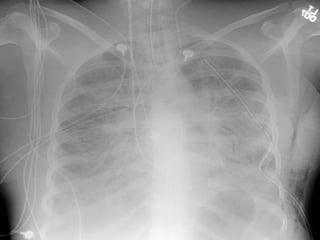

Clinical Observations Chest Wiggle Factor  CXR T8-9 Pulse oximetery TCO 2 ABG

Clinical Observations ChestWiggle Factor CXR T8-9 Pulse oximetery TCO 2 ABG